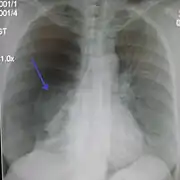

Chest X-ray

A plain chest radiograph, ideally with the X-ray beams being projected from the back (posteroanterior, or "PA"), and during maximal inspiration (holding one's breath), is the most appropriate first investigation.[30] It is not believed that routinely taking images during expiration would confer any benefit.[31] Still, they may be useful in the detection of a pneumothorax when clinical suspicion is high but yet an inspiratory radiograph appears normal.[32] Also, if the PA X-ray does not show a pneumothorax but there is a strong suspicion of one, lateral X-rays (with beams projecting from the side) may be performed, but this is not routine practice.[15][19]

Chest X-ray showing a pneumothorax on the right (left in the image), where the absence of lung markings indicates that there is free air inside the chest

Chest X-ray showing the features of pneumothorax on the left side of the person (right in image)

It is not unusual for the mediastinum (the structure between the lungs that contains the heart, great blood vessels, and large airways) to be shifted away from the affected lung due to the pressure differences. This is not equivalent to a tension pneumothorax, which is determined mainly by the constellation of symptoms, hypoxia, and shock.[13]

The size of the pneumothorax (i.e. the volume of air in the pleural space) can be determined with a reasonable degree of accuracy by measuring the distance between the chest wall and the lung. This is relevant to treatment, as smaller pneumothoraces may be managed differently. An air rim of 2 cm means that the pneumothorax occupies about 50% of the hemithorax.[15] British professional guidelines have traditionally stated that the measurement should be performed at the level of the hilum (where blood vessels and airways enter the lung) with 2 cm as the cutoff,[15] while American guidelines state that the measurement should be done at the apex (top) of the lung with 3 cm differentiating between a "small" and a "large" pneumothorax.[33] The latter method may overestimate the size of a pneumothorax if it is located mainly at the apex, which is a common occurrence.[15] The various methods correlate poorly but are the best easily available ways of estimating pneumothorax size.[15][19] CT scanning (see below) can provide a more accurate determination of the size of the pneumothorax, but its routine use in this setting is not recommended.[33]

Not all pneumothoraces are uniform; some only form a pocket of air in a particular place in the chest.[15] Small amounts of fluid may be noted on the chest X-ray (hydropneumothorax); this may be blood (hemopneumothorax).[13] In some cases, the only significant abnormality may be the "deep sulcus sign", in which the normally small space between the chest wall and the diaphragm appears enlarged due to the abnormal presence of fluid.[16]